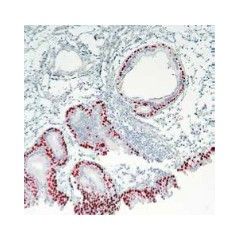

Description: Rabbit anti-p40, CE Certified (IVD) Isotype: IgG Immunogen: Synthetic peptide according to the amino acids residues 5-17 of human p40 Specificity: This antibody is designed for the specific localisation of p40 (or ΔNp63), a truncated p63 protein, in formalin-fixed, paraffin-embedded tissue sections. Anti-p40 antibody is intended for in vitro diagnostic use.

Technical Specifications: Pre-treatment: Heat Induced Epitope Retrieval (for example in EDTA Buffer pH 9.0)Control tissue: Lung squamous cell carcinoma Protocol: Working dilution 1:50-1:200 (for concentrates)